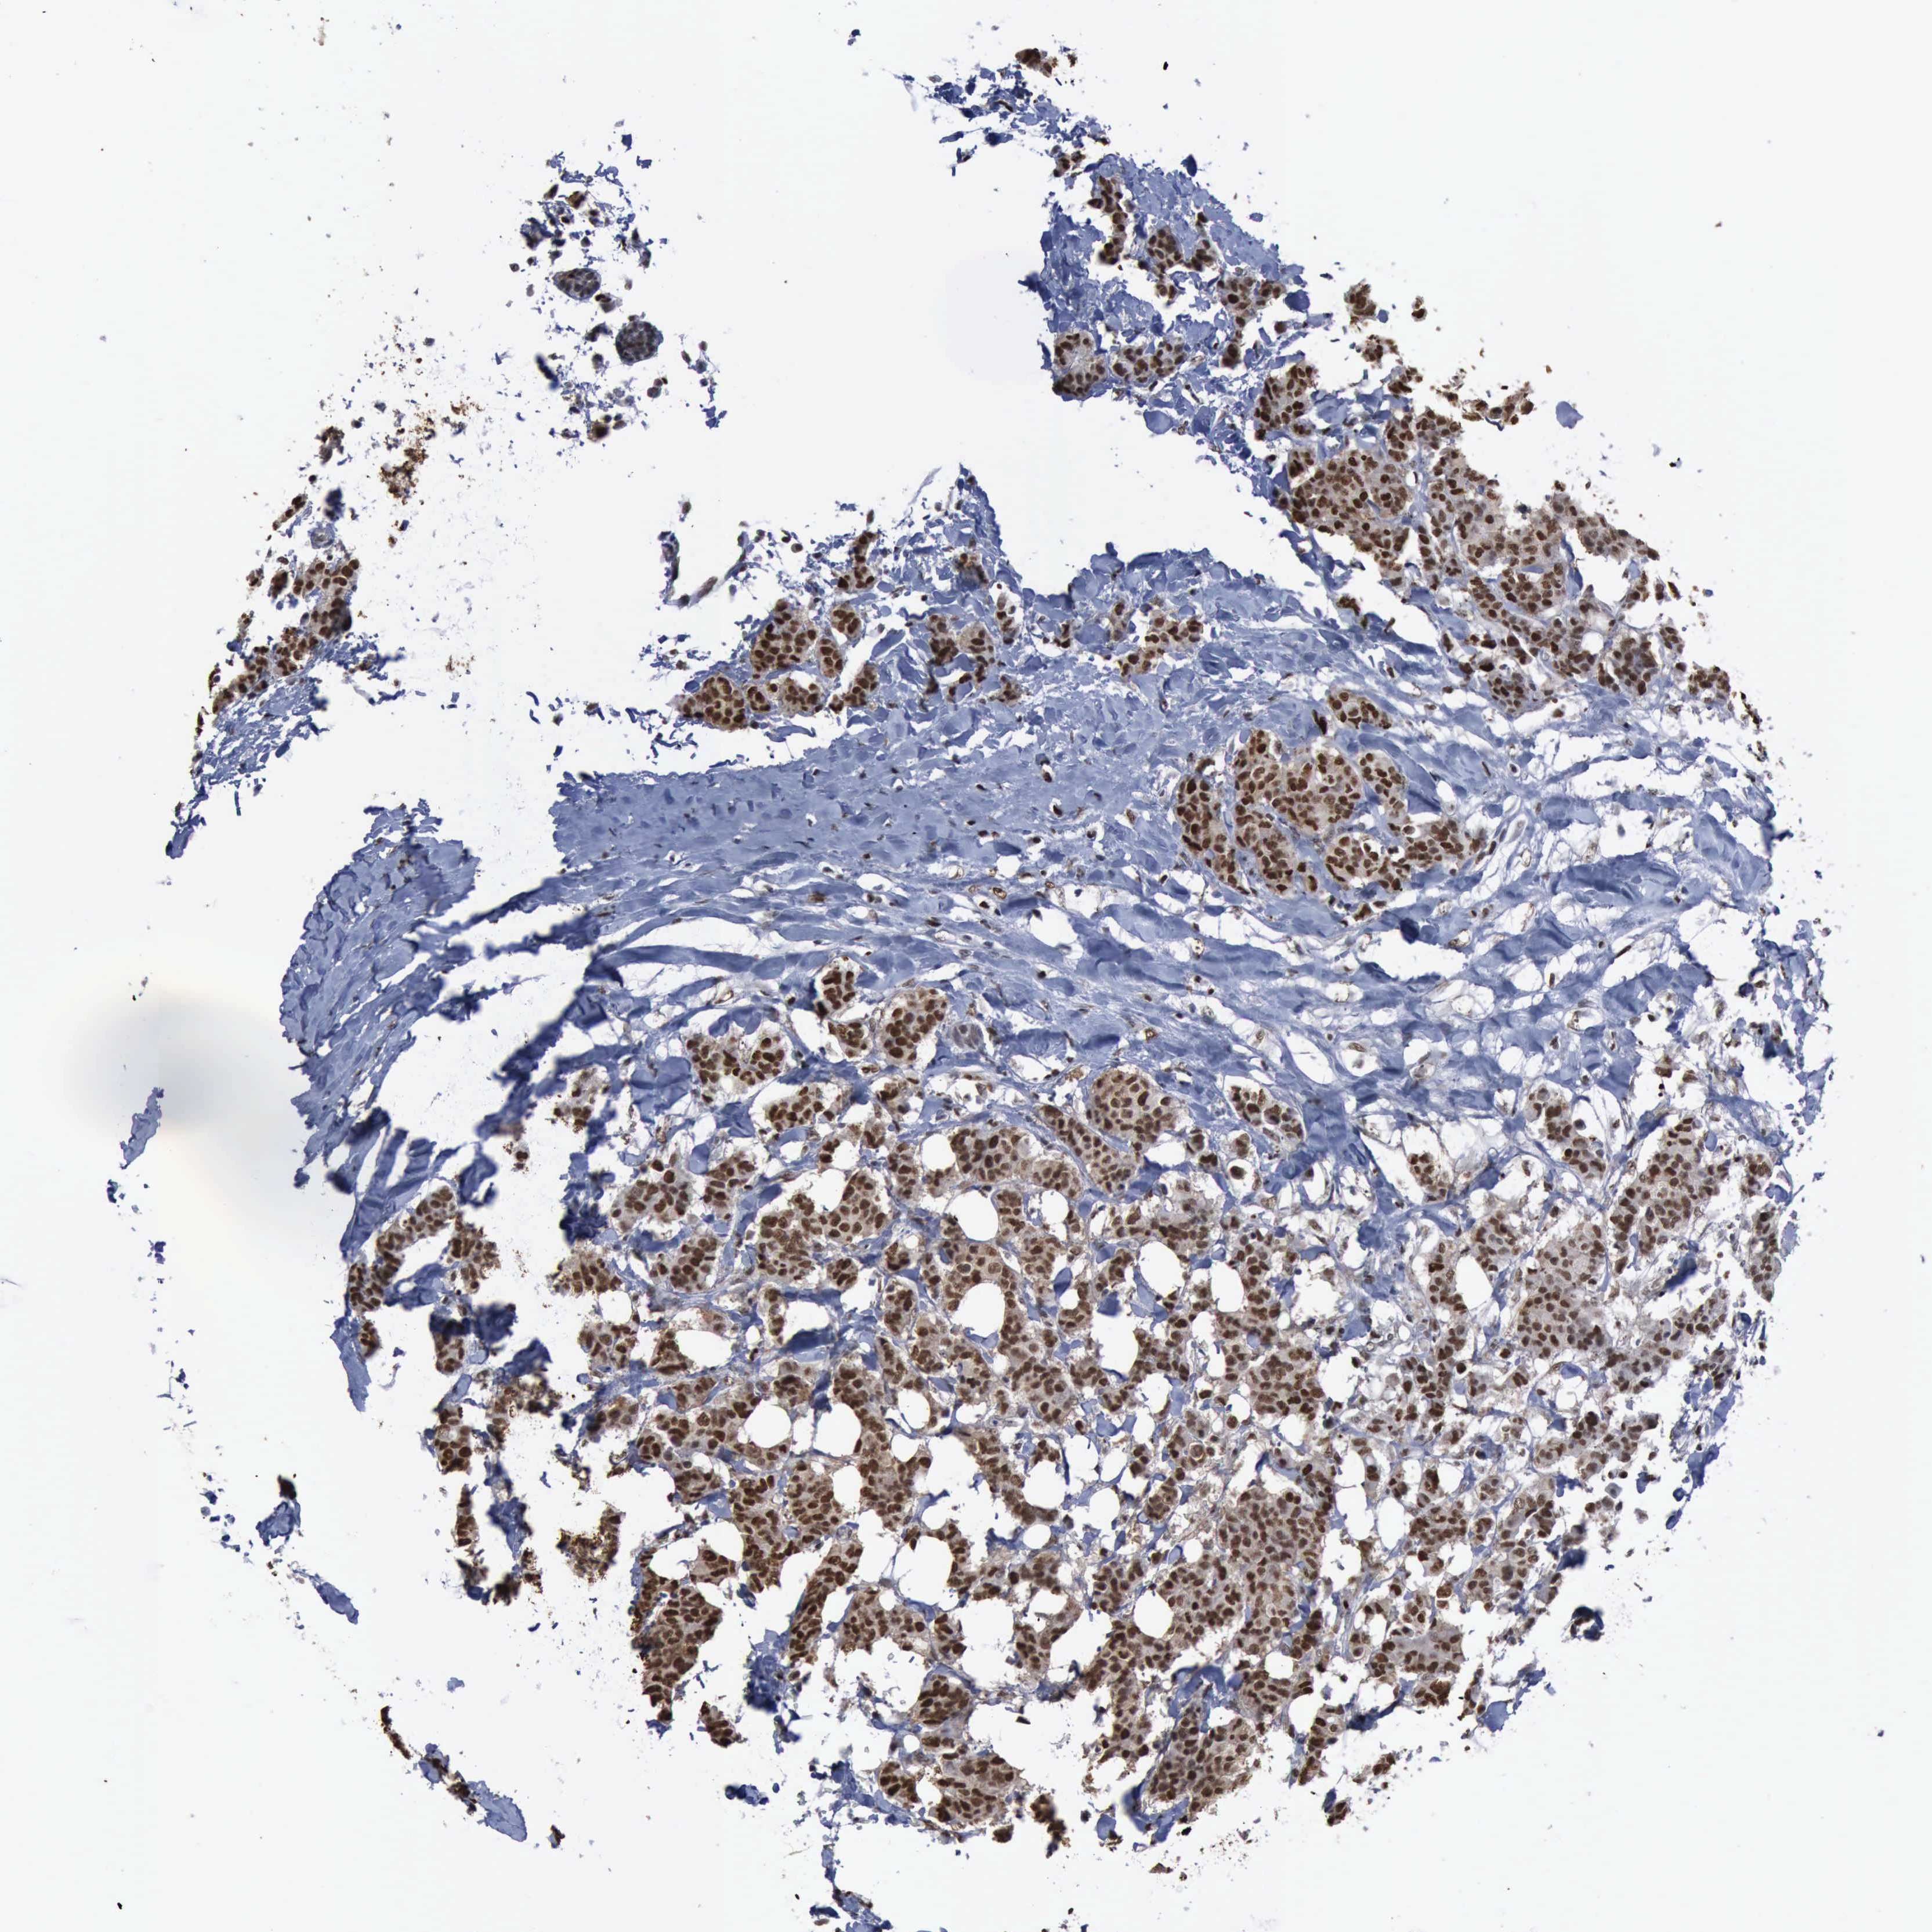

CANCER BREAST CANCER Show tissue menu

BRCA TCGA BRCA VALIDATION PROTEIN EXPRESSION

ANTIBODIES

AND

VALIDATION